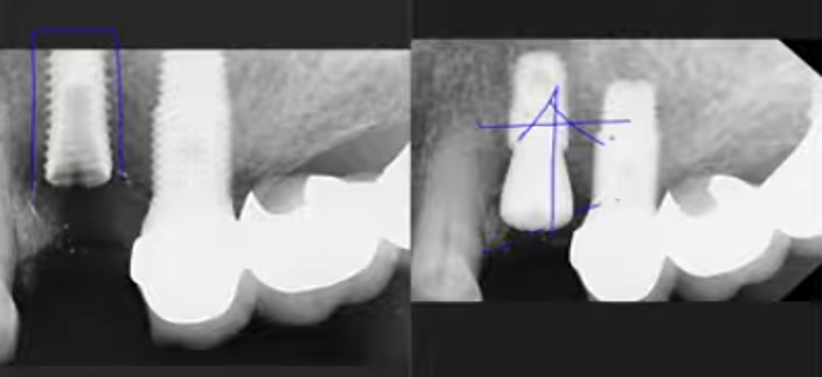

CASE.6 임플란트를 깊게 심어야 하는 이유..